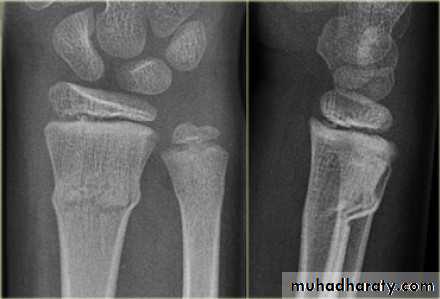

Upper limb

Fall on out stretched hand

xray

Possible complications

Ass n injury

Late complication